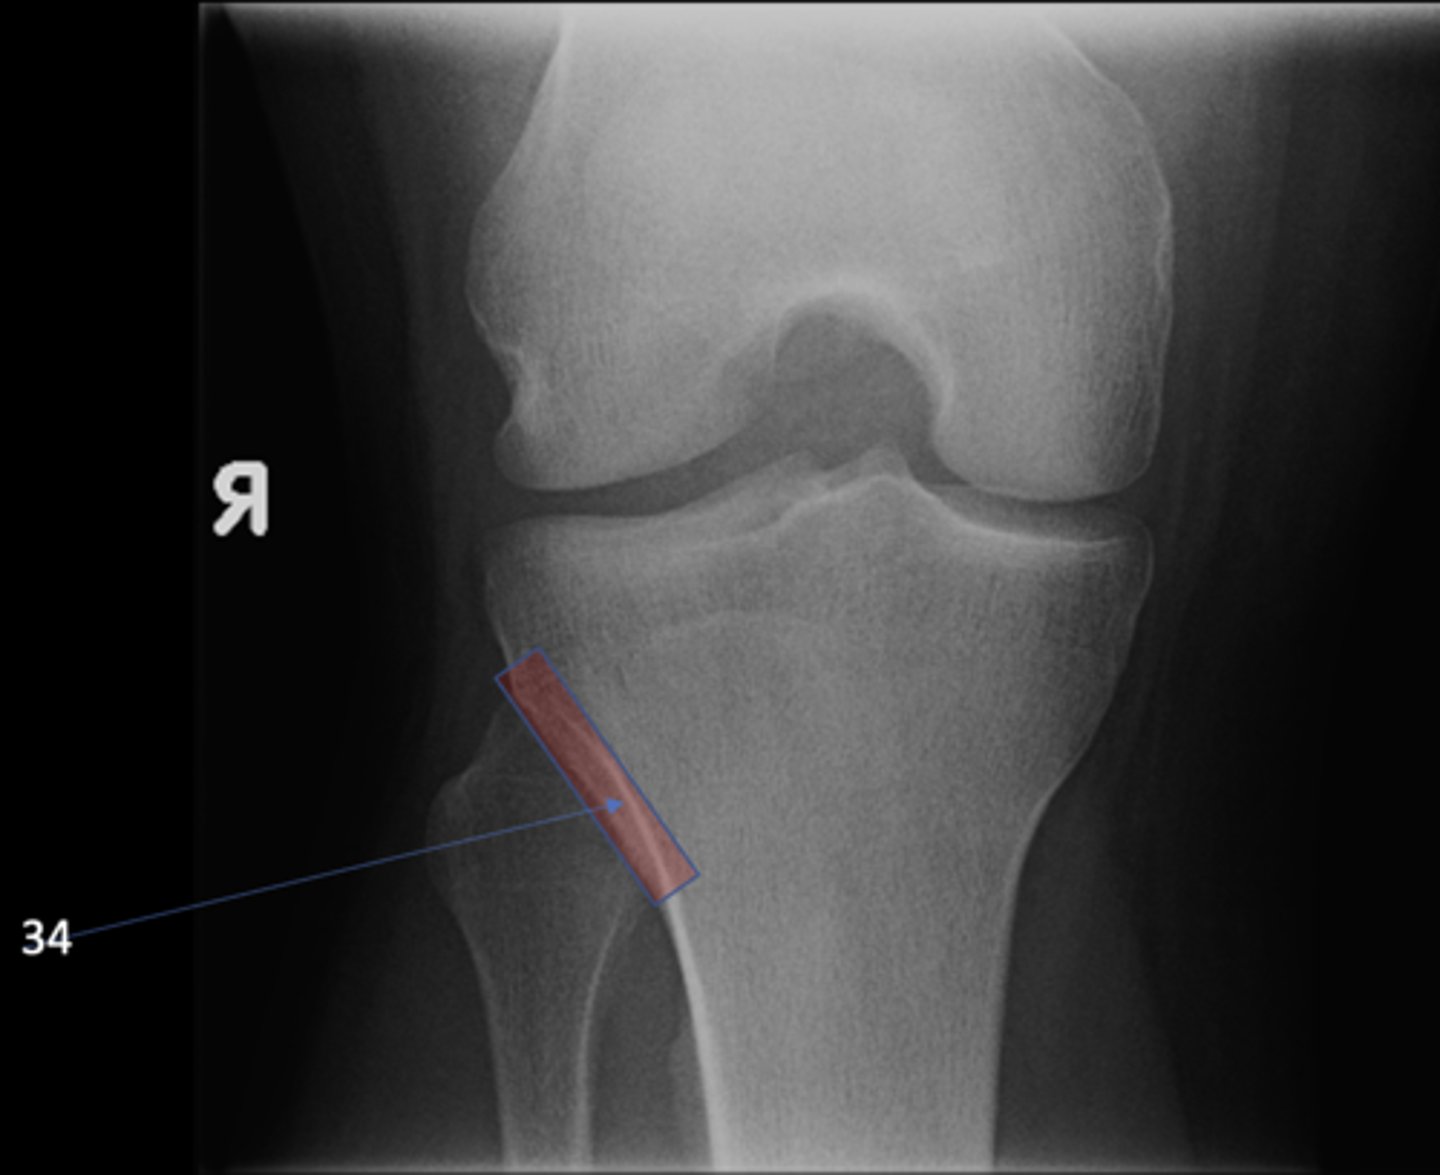

Lateral tibiofemoral joint

ID 33 (joint)

<p>ID 33 (joint)</p>

Proximal tibiofibular joint

ID 34 (joint)

<p>ID 34 (joint)</p>

Medial tibiofemoral joint

ID 35 (joint)

<p>ID 35 (joint)</p>

Patellofemoral joint

ID 36 (joint)

<p>ID 36 (joint)</p>